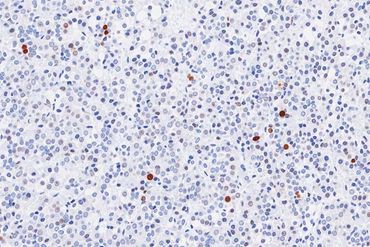

Currently used apoptosis assays include Terminal Deoxynucleotidyl Transferase Mediated dUTP Nick End Labeling of DNA (TUNEL) and Caspase-3 immunohistochemistry. DNA fragmentation is a part of ultrastructural changes that are associated with apoptosis. In TUNEL assay, the DNA strand breaks are detected by enzymatically labeling the free 3’-OH termini with modified nucleotides.

TPA currently uses proliferation assays that include Ki67, PCNA, BrdU IHC and In Situ Hybridization for Histone mRNA.